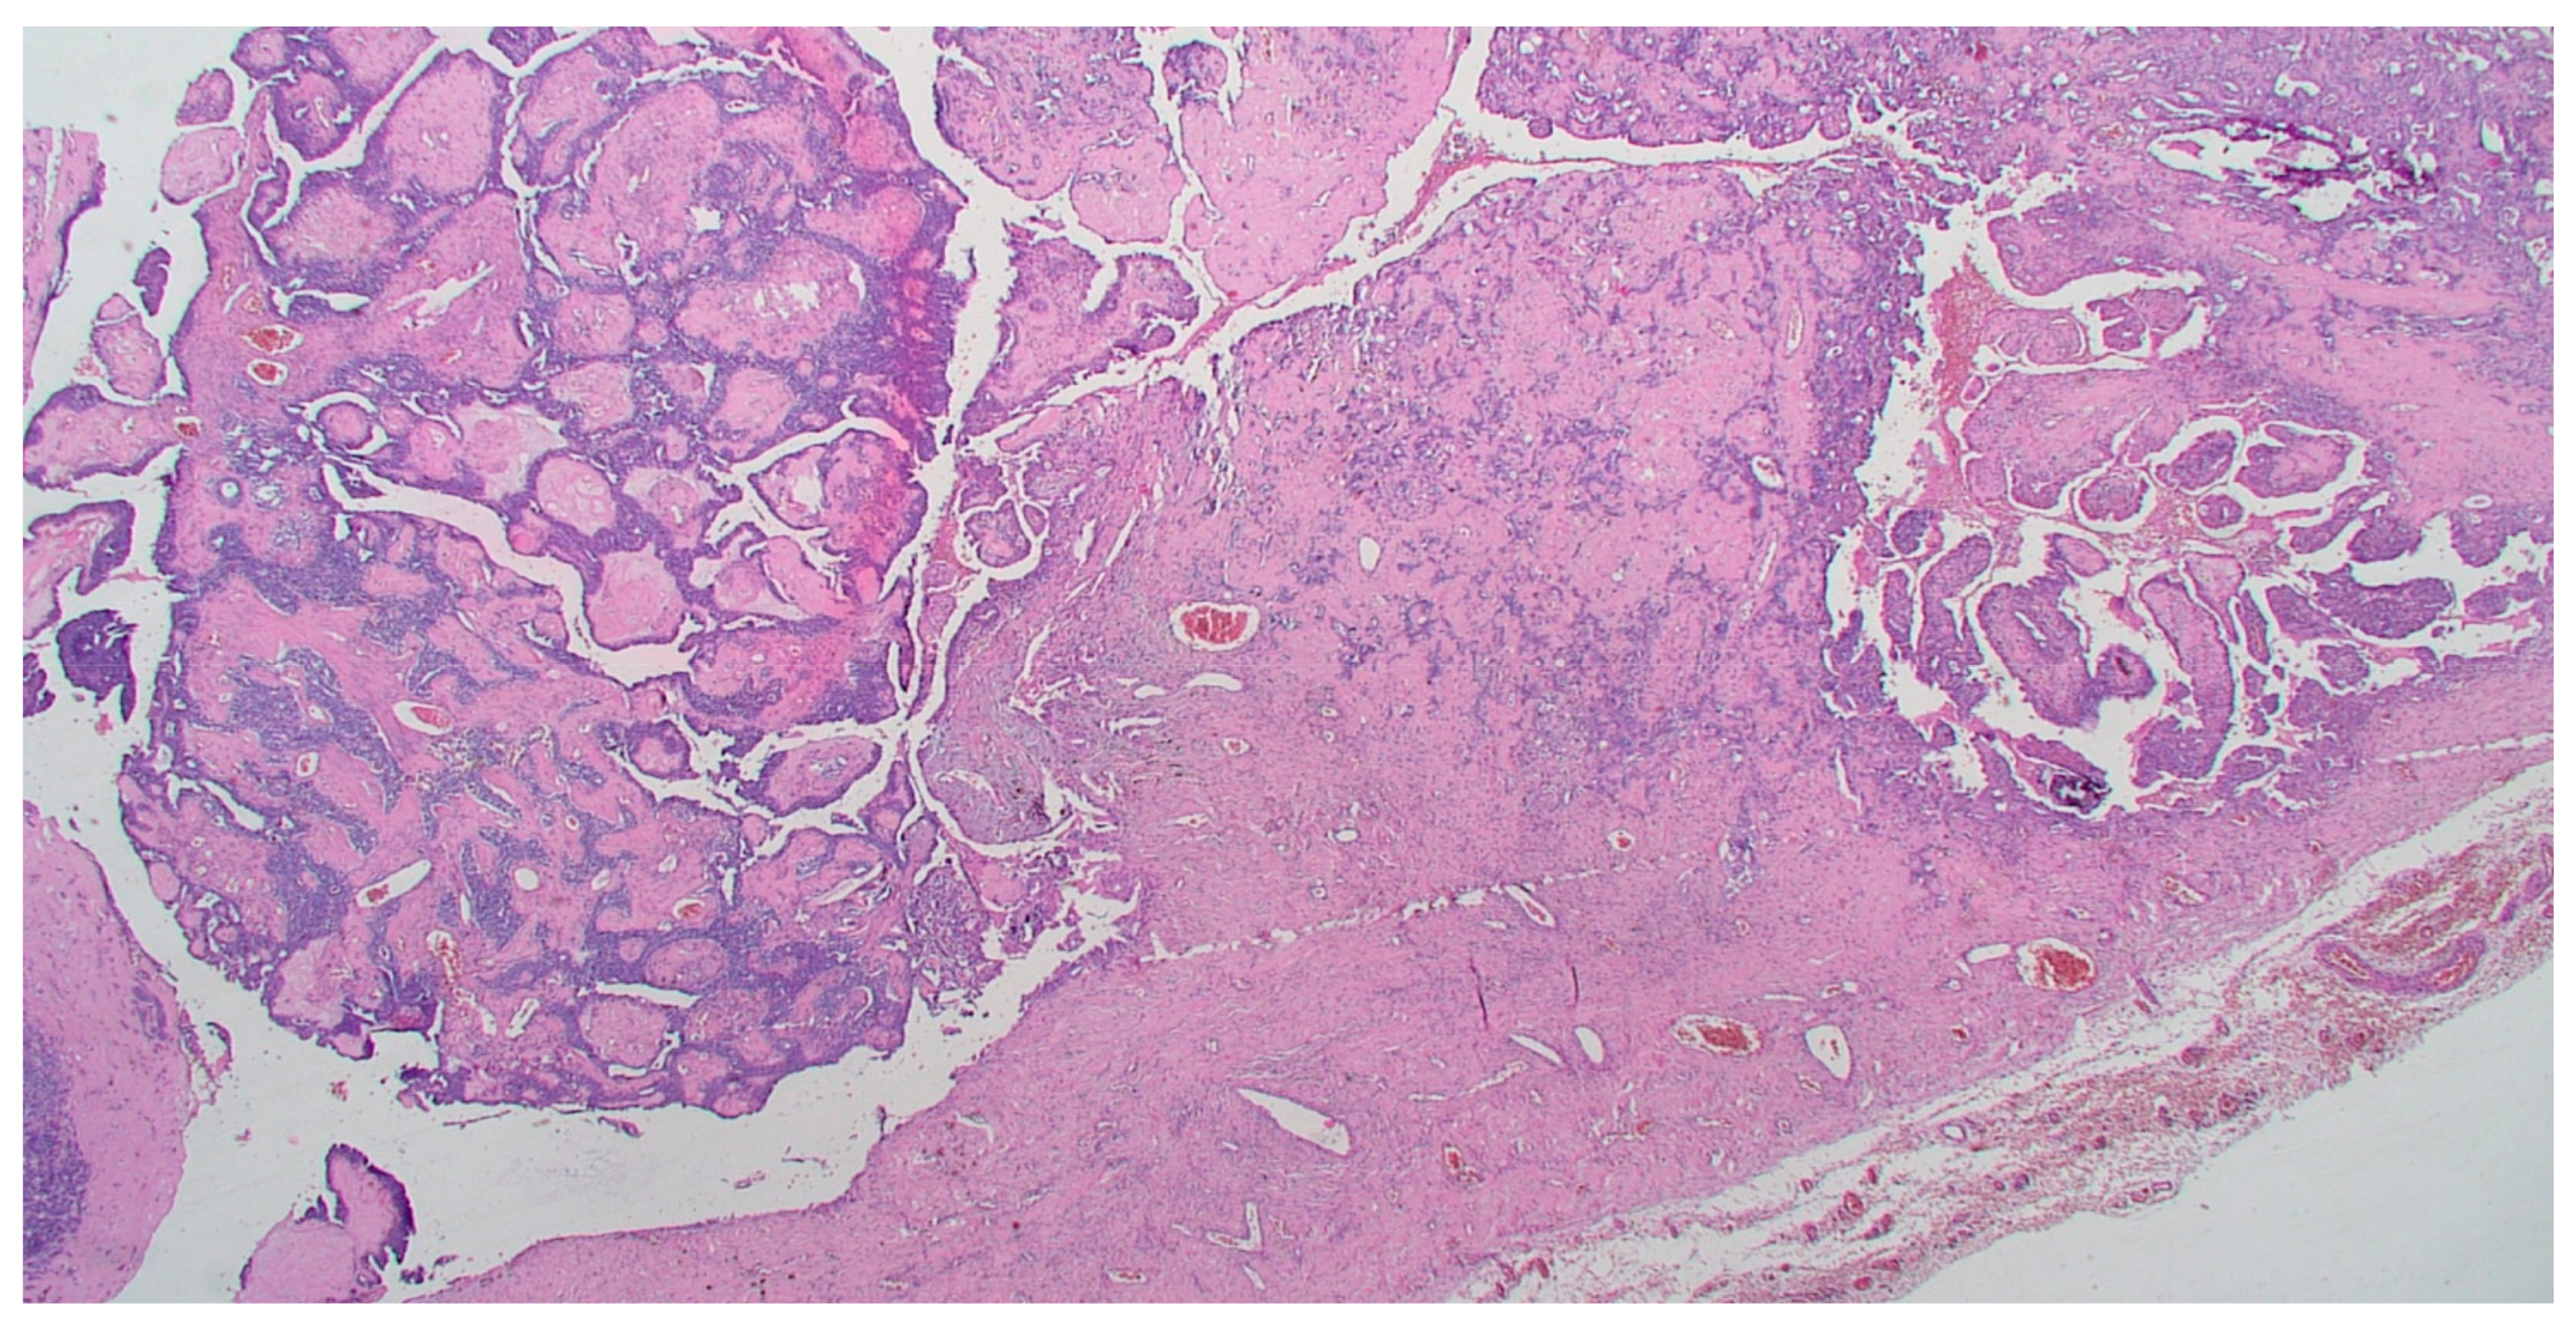

On gross pathology examination, the left ovary measured 4.5 × 3 × 2 cm, showing an intact, smooth outer surface. The cut section revealed a small unilocular cyst with an adjacent large, solid mass. The left Fallopian tube and the uterus were grossly normal. The omentum presented multiple nodules, the largest of which measured 4 cm. The resected large bowel segment showed a 5 cm nodule on the serosal surface. Histologically, the left ovary showed a serous cystadenoma, undergoing progressive transition to a serous borderline tumor and invasive carcinoma (Figure 1). The invasive part showed focal histological features of low-grade serous carcinoma (10%), but was mainly composed of a mesonephric-like adenocarcinoma (85%), showing tubular, glandular (pseudoendometrioid), sex cord-like and solid patterns (Figure 2). The tubular structures lumens contained typical eosinophilic colloid-like secretions. The nuclei were monomorphic, predominantly with vesicular chromatin and inconspicuous nucleoli. Focal lymphovascular invasion was present. There were no squamous or mucinous elements. However, a part of the neoplasm showed a chondrosarcomatous component (5%), intermingled with carcinomatous elements (Figure 3). The chondrosarcomatous component was observed also in the intestinal nodule, along with glandular and solid carcinomatous elements, infiltrating from the visceral peritoneum into the pericolic fat. The omental and peritoneal nodules revealed the same histological features as the ovarian mesonephric-like adenocarcinoma, without sarcomatous differentiation.

Figure 3. Chondrosarcomatous component intermingled with carcinomatous neoplastic cells. (HE, 200×).

Moreover, part of the tumor showed, both in the ovary and in the intestinal nodule, a mesenchymal malignant component consistent with a chondrosarcomatous appearance. In literature, some cases of uterine or vaginal mesonephric adenocarcinomas have been reported, associated with a sarcomatous component [12,13,14,15]. Neoplasms that contain both epithelial and mesenchymal malignant elements are defined as carcinosarcomas (previously known as malignant mixed Müllerian tumors), even though the mesenchymal component probably represents a metaplastic change of the epithelial component. Nevertheless, at the current state of the art, no cases of ovarian mesonephric-like adenocarcinomas have been found associated with a malignant mesenchymal component, before the case presented in this report. The immunophenotype of ovarian mesonephric-like adenocarcinomas, like the morphology, is similar to mesonephric adenocarcinomas of the female genital tract. They are usually positive for PAX8, negative for hormone receptors (ER and PR) and have a “wild-type” immunoreactivity for p53. Furthermore, they may show positivity for calretinin (nuclear and cytoplasmic staining), CD10 (luminal staining in tubular and glandular structures), TTF-1 and GATA-3 (both nuclear, usually focal) [16,17,18]. Our case showed a similar immunostaining profile in the mesonephric-like component, with positivity for CK7, Calretinin, CD10, TTF-1, GATA-3 and PAX8 and negativity for ER and PR. We also tested PD-L1 immunoreactivity, to see whether to attempt an immunotherapy treatment protocol along with adjuvant chemotherapy. By contrast, the low-grade serous part revealed positivity for ER and PR, along with negativity for Calretinin, CD10, TTF-1 and GATA-3, confirming the morphological appearance. Interestingly, the chondrosarcomatous component showed the same immunophenotype as the mesonephric-like component. This observation, never before reported in literature, may indicate a further step in the transdifferentiation process of these neoplasms, from Müllerian neoplasms to a mesonephric-like morphology and, finally, to a mesenchymal-like morphology. Another point of interest of this case is the focal CK7 positivity in the sarcomatous component. This finding suggests that the mesenchymal morphology may represent a metaplastic change of the carcinomatous part, rather than a true sarcomatous combined neoplasm, and also suggests that carcinosarcomas of the female genital tract are probably metaplastic carcinomas in which the mesenchymal part retains morphological and immunohistochemical features of the epithelial component.